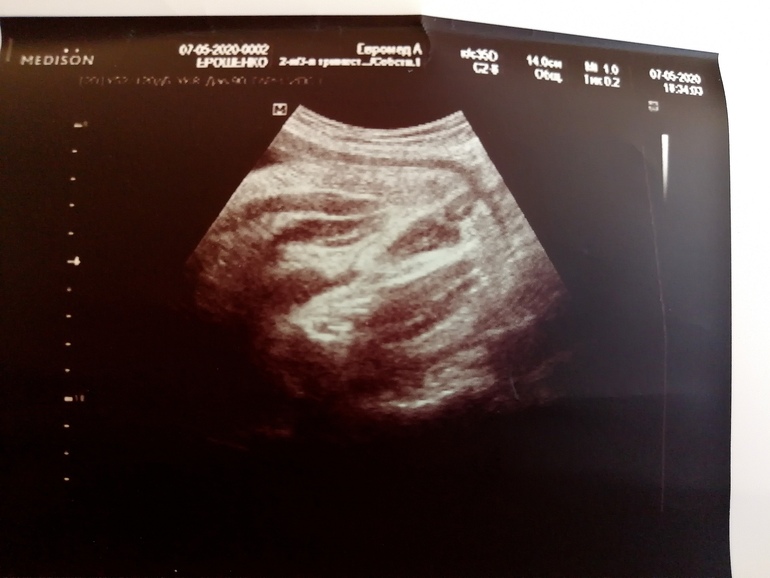

УЗИ шейки, контроль...33 недели ровно...

УЗИ, КТГ, доплерИ разве я не докапалась до Узистки чтоб она сделала фото😂.

Предыстория: человек общаться отказывался, лежала носом в мой позвоночник, личико прятала, попу тем более)

Сегодня успела прикрыть рукой рот, но мы ее поймали, не четко но есть какое ни какое фото), ну и "пирожок" тоже попался😂😂😂

На третьем я честно сама не понимаю что, на втором явно вижу кофейное зёрнышко, ну и Узистка без сомнений 100% сказала Мадама сидит стеснительная)))

Сколько нынче шейка) я до 34 недель тоже мониторю и всееее) дальше неинформативно)

43 мм, у меня шейка и с двойней до последнего была длиннющая, надеюсь и тут не подведёт, после 35 ложусь в роддом, там уже под присмотром не страшно)

В начале у меня почти 5 была, 2 недели назад 45, сейчас 43🙈